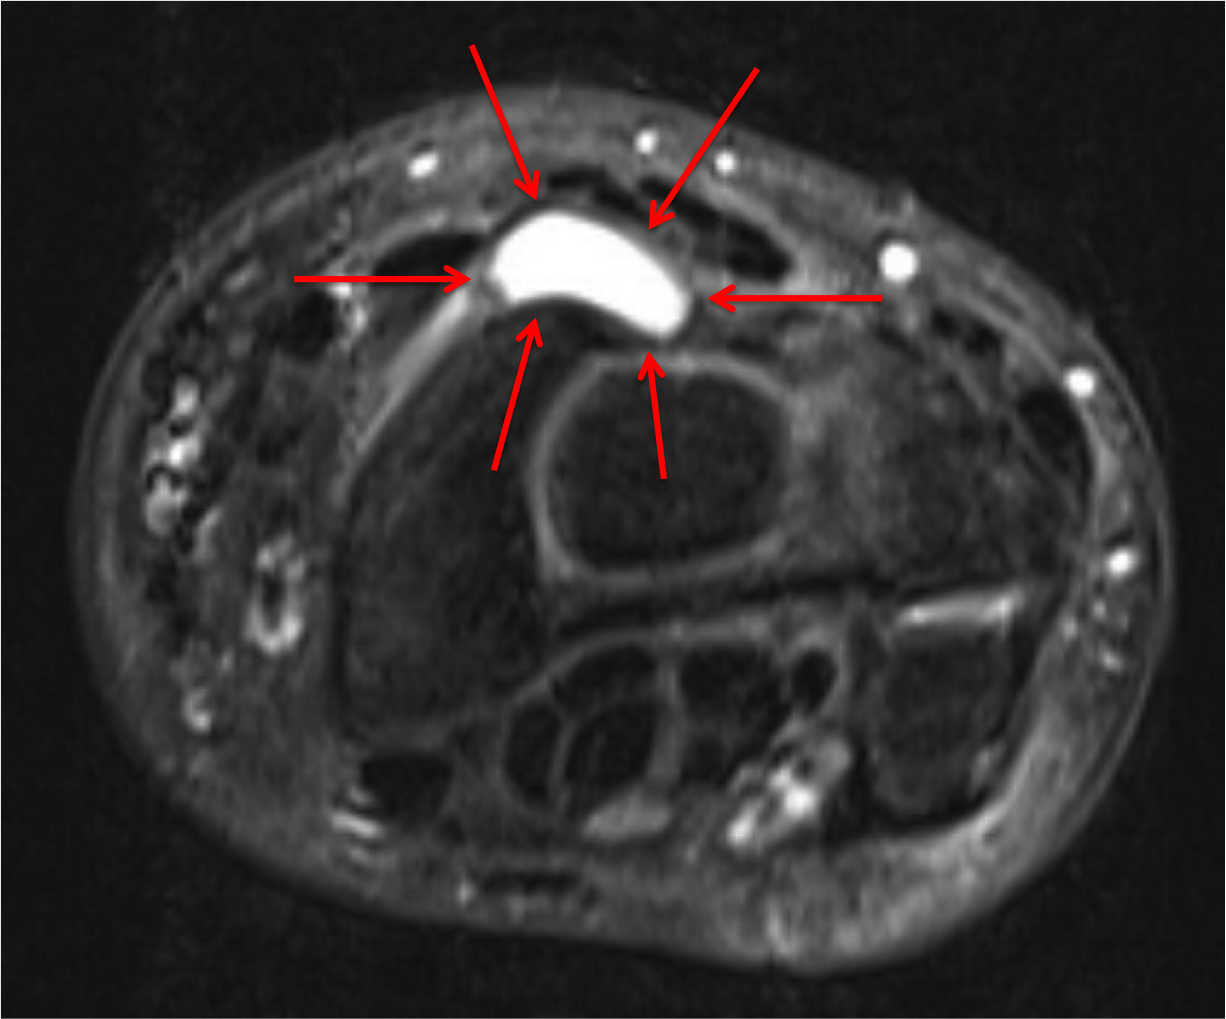

Mucous Cyst of the Finger Diagnosis and Treatment Finger Joint Ganglion Cyst ganglion cysts of the hand and other joints are more likely to affect women than men, and more likely to appear in patients. a ganglion cyst is a small sac of fluid that forms over a joint or tendon (tissue that connects muscle to bone). a ganglion cyst starts when the fluid leaks out of a joint. Finger Joint Ganglion Cyst.